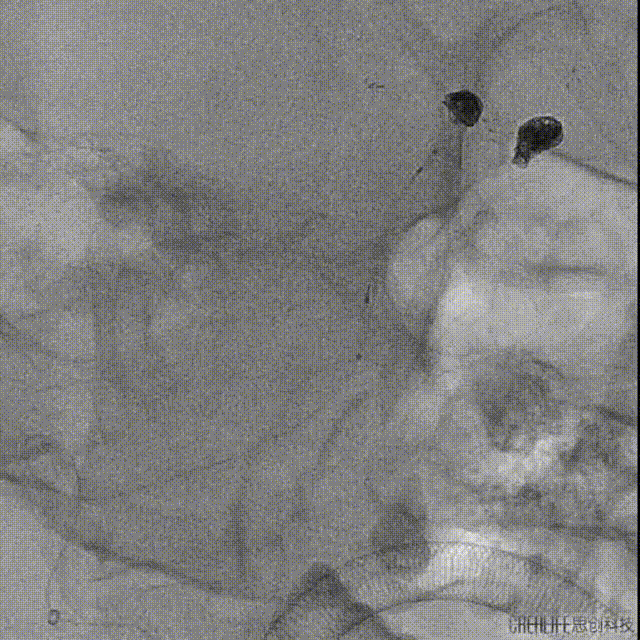

手术精华

右颈内动脉造影复查,前交通动脉瘤愈合良好,未见复发。

建立通路:6F长鞘到位右侧椎动脉开口处,微导管微导丝+V18导丝支撑,同轴技术下将6F中间管送达右侧椎动脉V3段。

证实基底动脉多发狭窄并中段瘤样扩张,基底动脉尖动脉瘤,左侧椎动脉V4段重度狭窄,狭窄程度90%。

3D造影

工作位

路图及微导丝指引下将塑形J形SL-10微导管送达右侧大脑后动脉。

另选塑形Echelon 10微导管送至瘤体处,填塞Prime弹簧圈5*15mm。

经SL-10微导管推送Atlas支架4*24mm,半释放支架并充分覆盖瘤颈,继续填塞弹簧圈并解脱。

依次填入Prime弹簧圈3*6mm、3*6mm、2*4mm、1.5*2mm,将Atlas支架完全释放。

正侧位造影,见瘤体填塞致密。